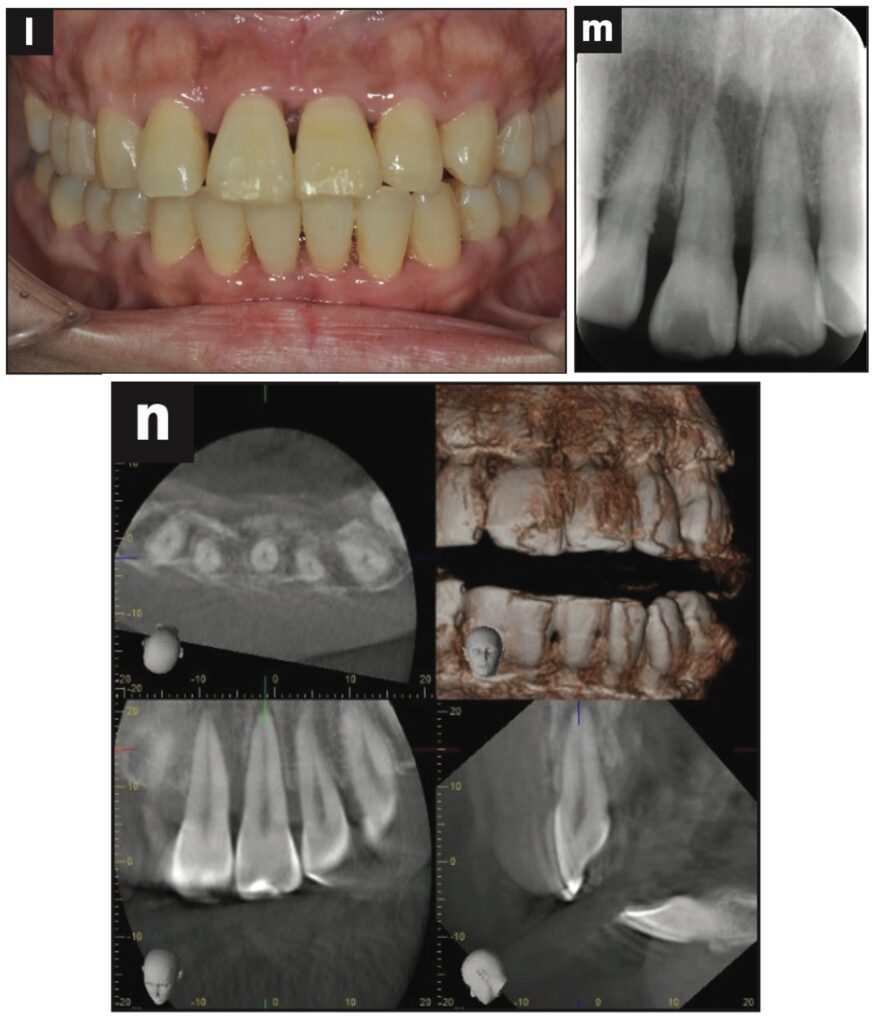

Bệnh nhân nữ 42 tuổi bị ngã khiến răng cửa giữa hàm trên bên trái bị lệch về phía vòm miệng. Đường gãy xương ổ răng ở phía khẩu cái được thấy trên CBCT.

Răng được nắn chỉnh và cố định bằng composite quang trùng hợp rồi lấy dấu. Hai tiếng sau, bệnh nhân quay lại và nhận khay duy trì. Bệnh nhân được hướng dẫn đeo khay duy trì cả ngày trừ khi đánh răng.

Các thử nghiệm tủy được thực hiện sau 7 và 28 ngày. Đánh giá độ lung lay răng, gõ và sờ, thử tủy EPT và chụp X quang được thực hiện sau 28 ngày.

Sau 28 ngày theo dõi, răng hơi lung lay và không đáp ứng với thử tủy EPT. Sau 2 tháng theo dõi, răng không bị đổi màu, không lung lay, âm tính với EPT và hơi nhạy cảm khi gõ. Không có tổn thương quanh chóp trên X quang và không có lỗ dò. Sau 3 tháng theo dõi, răng đã đáp ứng với EPT (9/10) và có cảm giác đau nhẹ khi gõ.

Sau 4 tháng theo dõi, răng đã phản ứng với EPT (9/10) và không còn nhạy cảm với gõ.